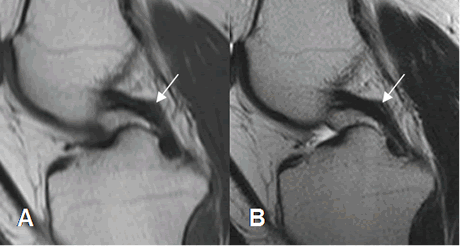

El LCP también se aprecia como una banda hipointensa en todas las secuencias. (2). (Fig 17). El ángulo entre los ejes de la inserción tibial y femoral, normalmente mide 123º. (11).

Este ligamento está rodeado por los ligamentos meniscofemorales que se originan del cóndilo femoral interno y se insertan en el menisco externo. Son el anterior o de Humphrey y el posterior o de Wrisberg. Estas estructuras no deben confundirse con cuerpos libres intra-articulares. (2). (Fig 18 y 19).

Fig 18. Ligamentos meniscofemorales.

A y B: RM sagital en T1. Ligamento meniscofemoral anterior (Flecha delgada) y posterior (Flecha gruesa).

Fig 19. Ligamentos meniscofemorales normales.

A: RM coronal en T1 y B: RM coronal en STIR. Ligamento menisco femoral posterior (Flecha delgada), en relación con el LCP (Flecha gruesa). Menisco externo (Punta de flecha).